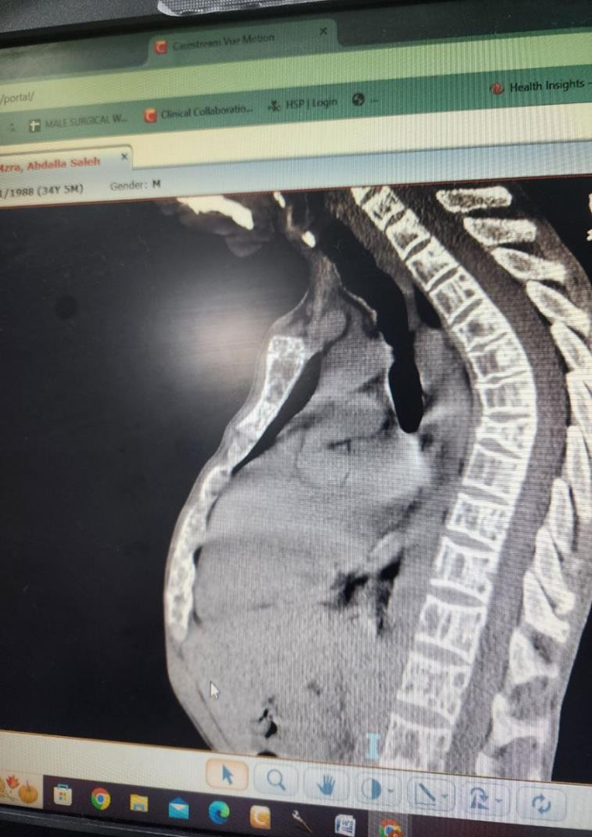

His recent condition started two months ago when he presented with a right humeral pathological fracture, which did not union after two months of management. Then, thorough investigations were done to determine the cause of his pathological fractures. His laboratory test is shown in Table 1. His chest x-ray showed osteoporotic features. His extremities and vertebrae showed osteoporotic features. At the T99m MIBI nuclear scan, a focal and persistent active spot at the lower pole of the right thyroid gland, consistent with parathyroid adenoma, was detected (Figure 2).

There are striking similarities between clinical and laboratory findings of pHPT from Iran and other eastern regions [8, 9]. Testing of intact PTH level is the core of the diagnosis of hyperparathyroidism [3]. Elevated PTH and serum-ionized calcium levels are a diagnostic method for pHPT [4]. A 24-hour urinary calcium measurement is necessary to rule out. Figure 2: The T99m nuclear scan shows a focal and persistent active spot at the lower pole of the right thyroid gland, consistent with parathyroid adenoma. out familial hypocalciuric hypercalcemia [4]. Patients with pHPT usually excrete more than 200 mg calcium per 24- hour, a calcium/creatinine clearance ratio.

Imaging studies are not used to diagnose, confirm, or decide on surgical therapy of hyperparathyroidism [9, 10]. If a limited parathyroid exploration is to be attempted, a localizing study is necessary [9–11]. In patients who have recurrent or persistent hyperparathyroidism after a previous surgery, an imaging study will be necessary [12], in which the T99m nuclear scan is the best initial test [4, 10]. T99m nuclear scan is highly specific for abnormal parathyroid tissue, and its sensitivity is more than 90% in solitary adenoma, but in multiglandular disease, its sensitivity is very low (55%) [10].